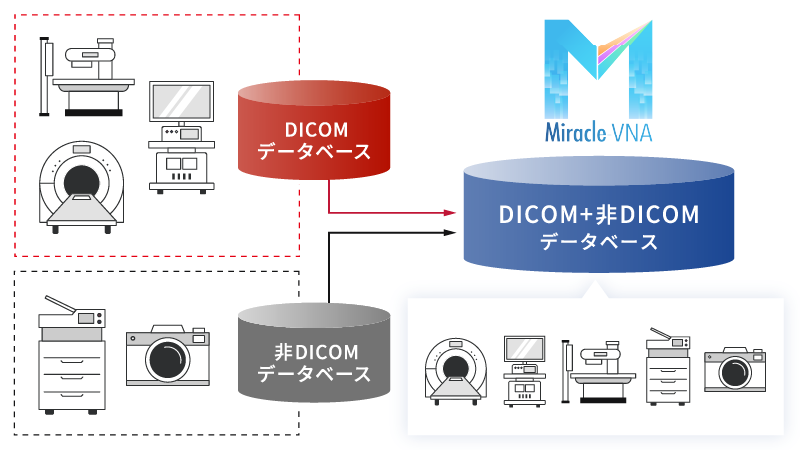

DICOM/非DICOMデータを一元管理

DICOM/非DICOMデータを一元管理

DICOMだけでなく、非DICOMデータや他の標準フォーマットもサポート。

異なるPACSやEMRシステムとシームレスに連携できる機能で、互換性を最大限確保します。

基本パッケージのコストを最小限に抑え、データベースの一元化によって効率的なストレージ構成を組んだ最先端のシステムをご提供いたします。